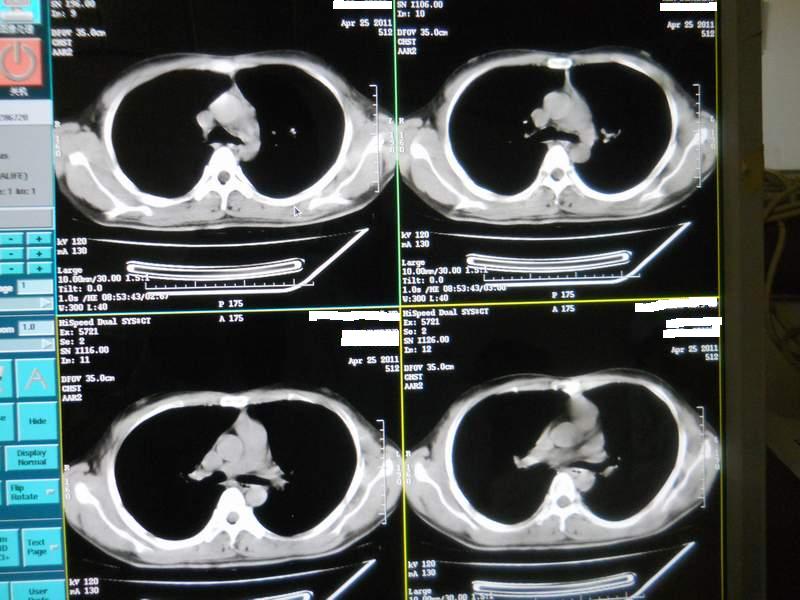

肺霉菌感染

男,22岁,一年前诊断马尔菲尼青霉菌感染,多次复查CT。多次HIV阴性。最近两次CT图片。有实验室结果。

最近实验室检查结果:霉菌感染。